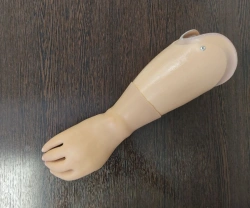

Foot Shell for Carbon Fiber Prosthetic Foot 9H02

US$90-300

Size:

22...30

Weight:

160...290

METIZ PRODUCTION LLC 🇷🇺